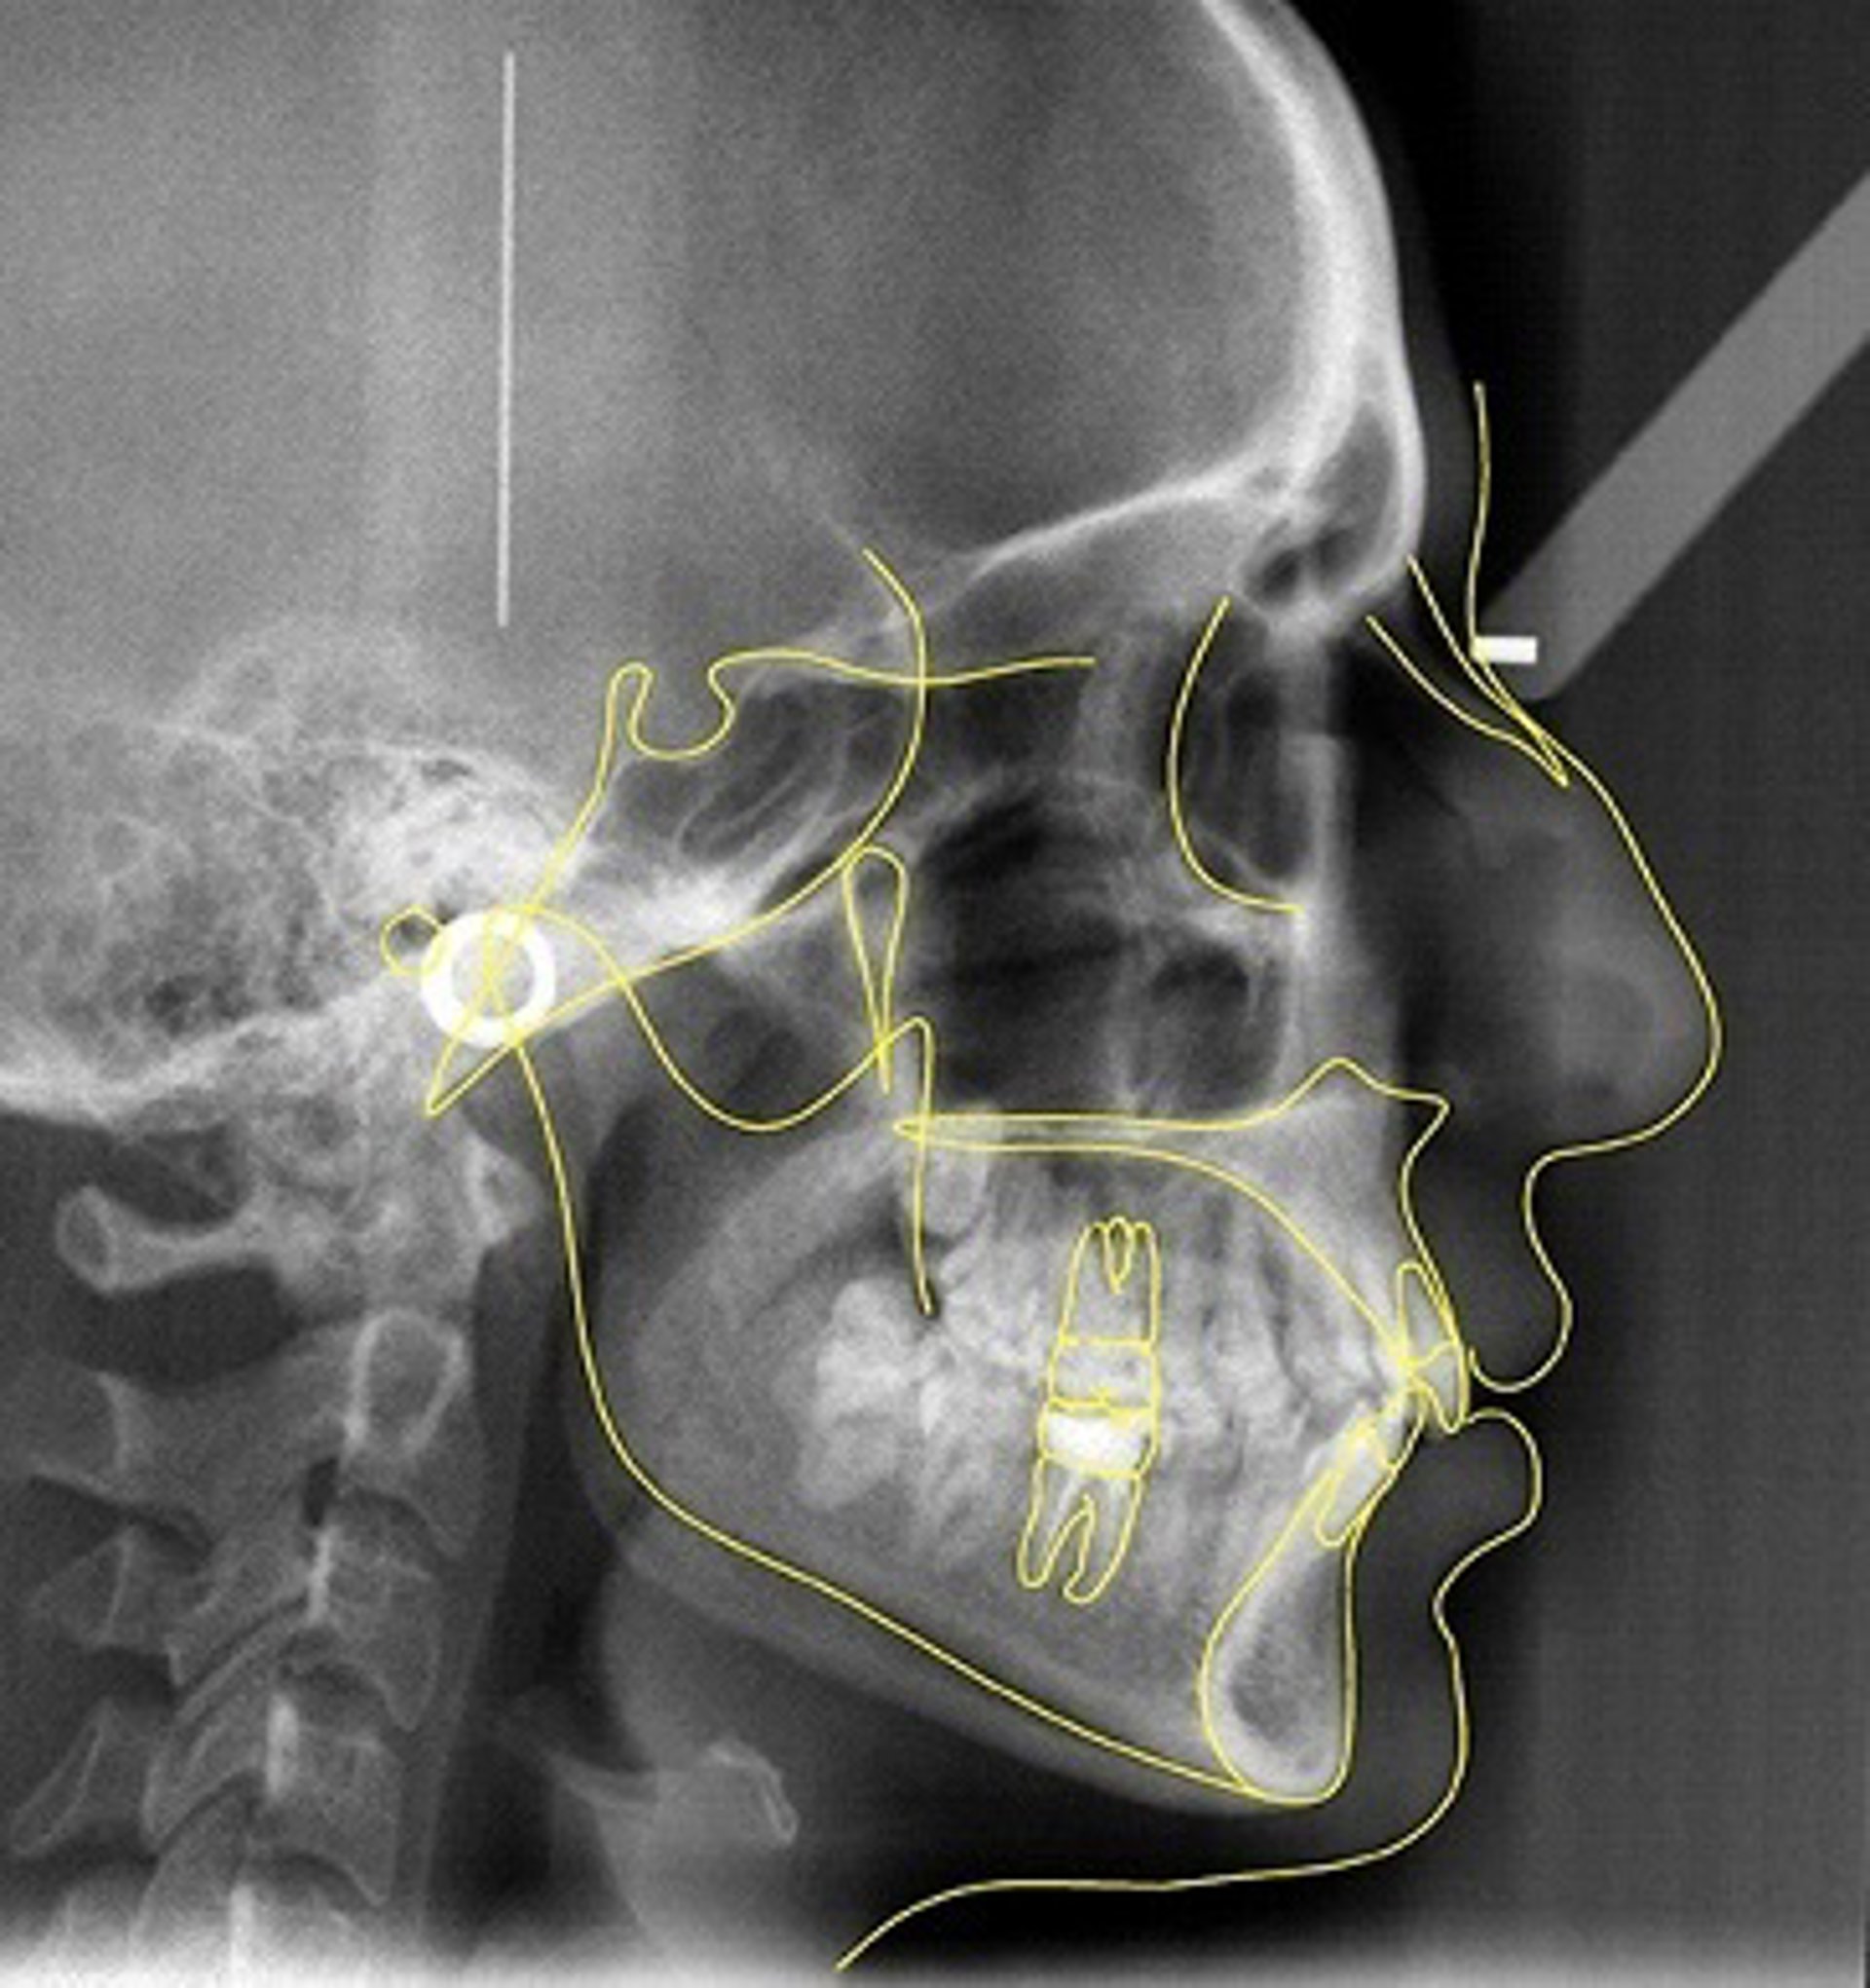

Trazado cefalométrico superpuesto en la Telerradiografía lateral del Cráneo

Los estudios de cefalometría se llevan a cabo mediante un 'software' informático y una plataforma de control de registros de última generación y tecnología de vanguardia.